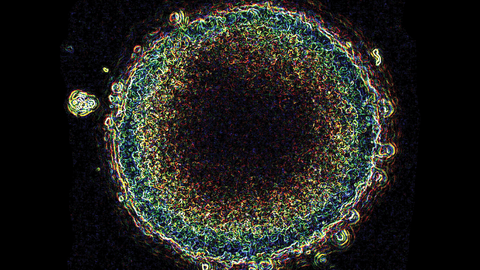

On 30 June, the ACRF Intravital Imagine of Niches for Cancer Immune Therapy (INCITe) Centre was officially launched. This centre houses two Australian-designed, world-leading microscopes that allow researchers to observe the interactions between cancer cells and the immune system in real time, providing greater insight into how drug-resistant, dormant cancer cells develop and function.